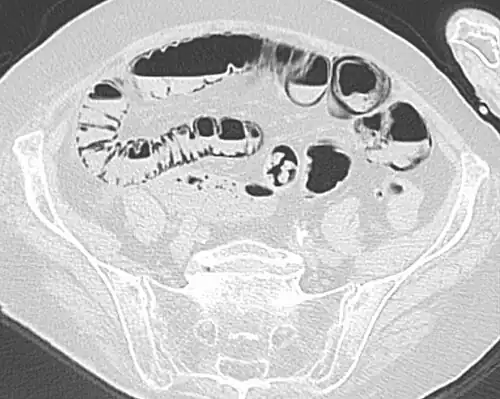

Pneumatosis intestinalis at computed tomography in intestinal ischemia. Lung window for better representation of the gas deposits in the intestinal walls. Coronal reconstruction. -

Pneumatosis intestinalis in computed tomography with intestinal ischemia. Lung window for better representation of the gas deposits in the intestinal walls. -